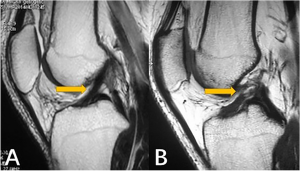

تشخیص شامل معاینه بالینی، تستهای فیزیکی مثل تست لاخمن و تست کشوی قدامی، و استفاده از روشهای تصویربرداری مانند MRI است. فیزیوتراپیست یا پزشک متخصص پس از ارزیابی کامل، برنامه درمانی مناسب را انتخاب میکند.

عکس سمت چپ ACL نرمال

عکس سمت راست ACL پاره